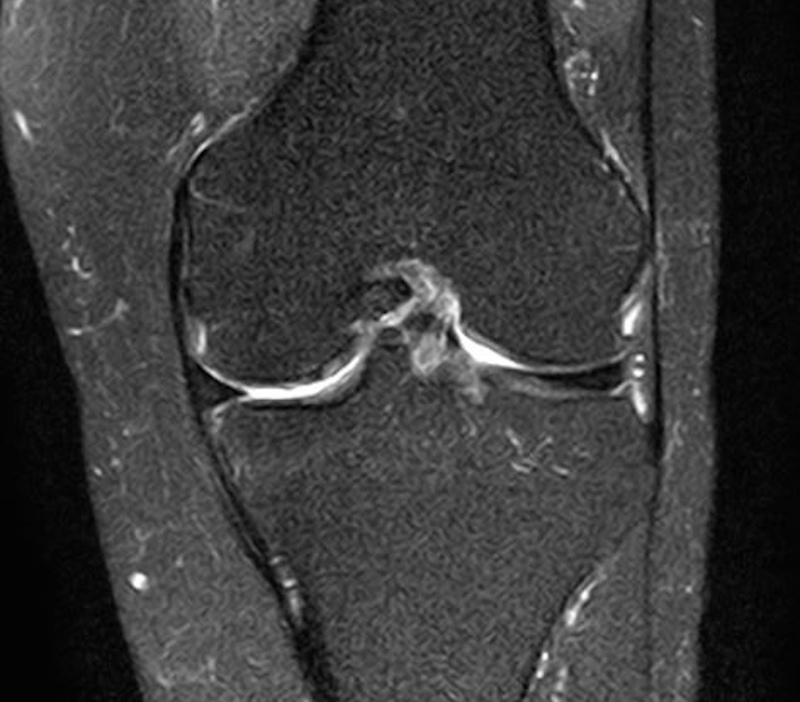

MRI検査

超音波検査